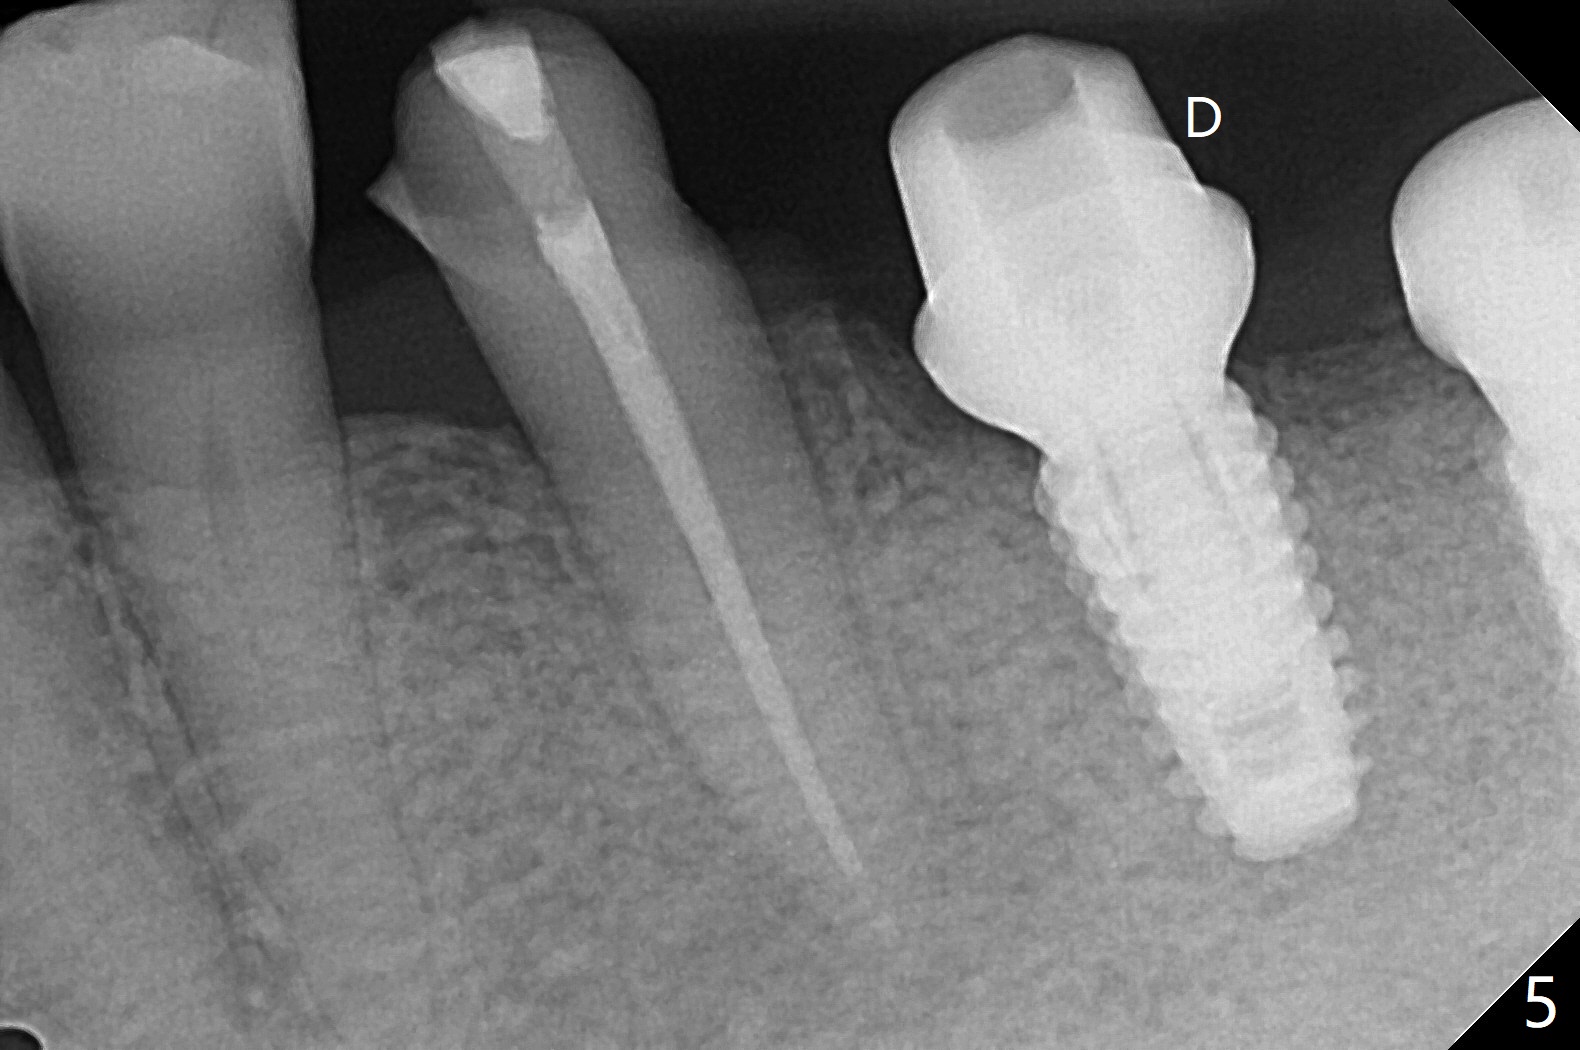

18,19导板远中架在17号牙残根表明树脂(图二:S),起到防止下沉作用,18号牙植体(~35Ncm)使用植体固定钉(fixture anchor mount no stop)植入,后者并且起着固定导板作用,增加19号牙植体植入稳定性,术中根尖片(图一)显示19号牙钻洞还不够深,之后钻头增加长度1.5毫米,4.5x8.5毫米植体扭力15-20Ncm(图二),但是与下齿槽神经管(红色虚线)还有很大距离,可能导板没有完全就位,植入后应该马上再次拍摄根尖片证实植入深度。由于18号牙区角化龈特别狭窄,切开种植,另外一个好处是容易植骨,但是术后疼痛明显,与上前牙即刻植牙(无切开)相比。今后尽量多做即刻种植。不过术后3个月包埋的植体表面有骨质覆盖(图三:*),二期手术很难找到愈合帽,而早些种植的上前牙植体由于过早受力,愈合不佳。当修复基台平面朝向颊侧,基台没有完全就位(图四:>)。当平面面对远中(图五:D),基台好像就位。